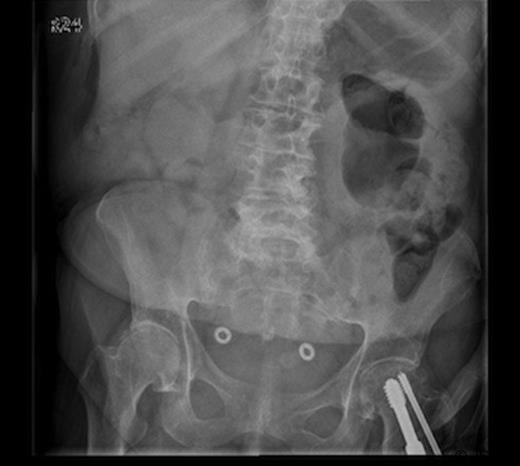

Plain abdominal radiograph showed a non-dilated, gas-filled loop of large bowel in the left upper quadrant, but no free gas within the peritoneal cavity (fig1). The erect chest radiograph demonstrated ectasia of the thoracic aorta but no subphrenic gas.

Plain abdominal radiograph showing a non-dilated, gas-filled loop of large bowel in the left upper quadrant, but no free gas within the peritoneal cavity